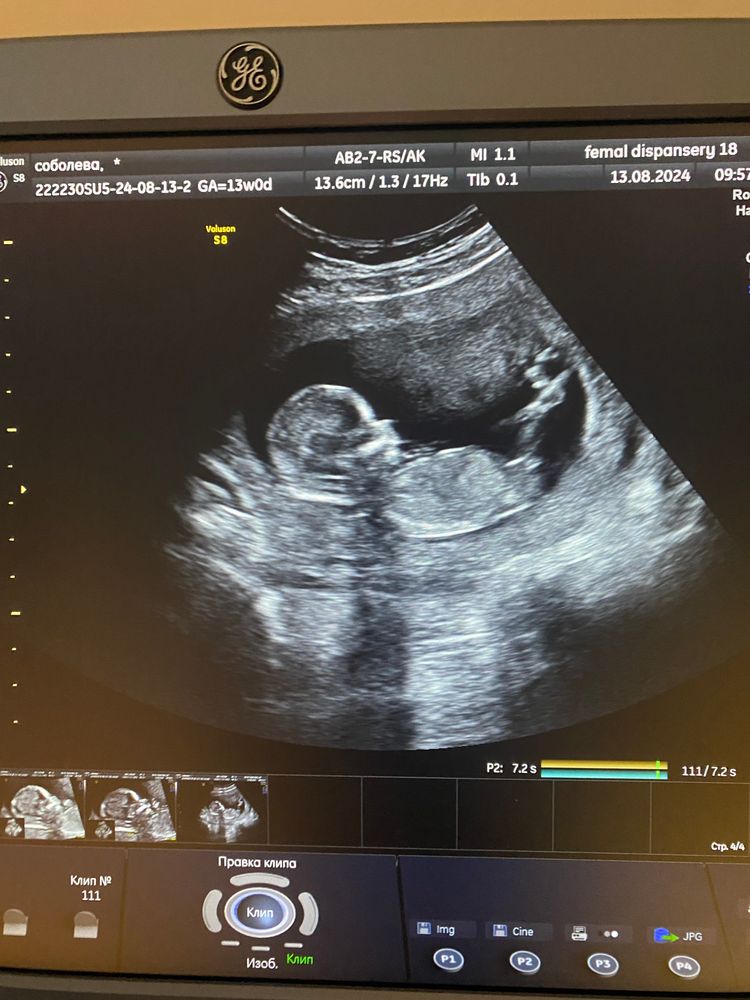

Мальчик или девочка ?

У моего так же бугорок расположен. Тут на бб единогласно сказали, что девочка) Изображение

Девочка по положению полового бугорка)

Мне кажется у вас девочка)))У нас прям вверх торчит, предположил врач сразу же мальчишку)))